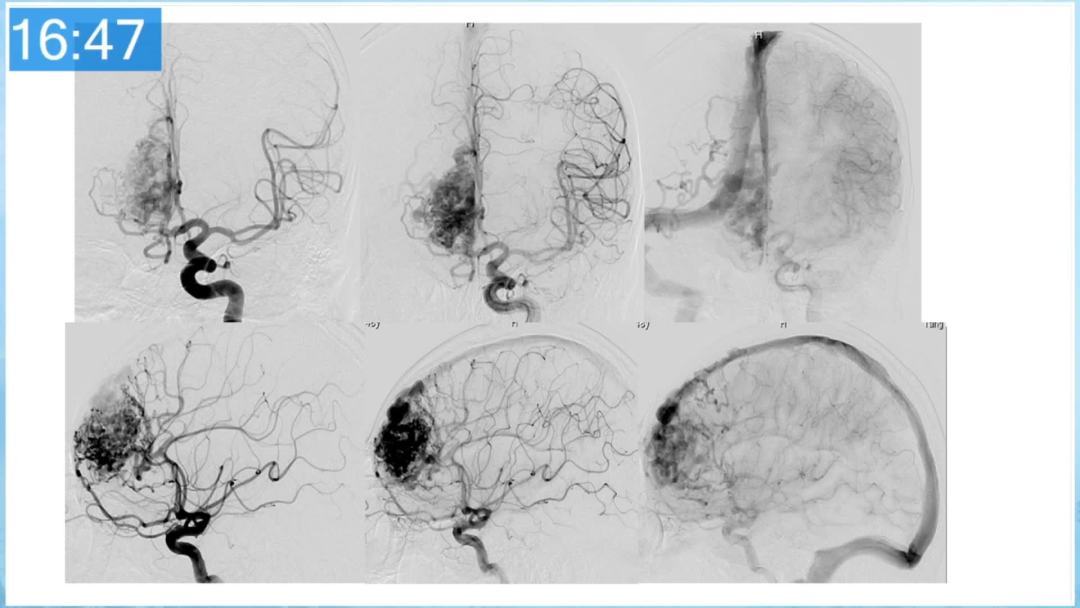

合理的复合平台下的综合治疗,针对每一个病变对应不同方法安全性分析,不预设、不排斥,每种技术发挥到最佳,互相保障。

本期为大家特别分享:空军军医大学唐都医院邓剑平教授的精彩会议内容《颅内动静脉畸形的复合手术治疗》,欢迎大家阅读和分享!